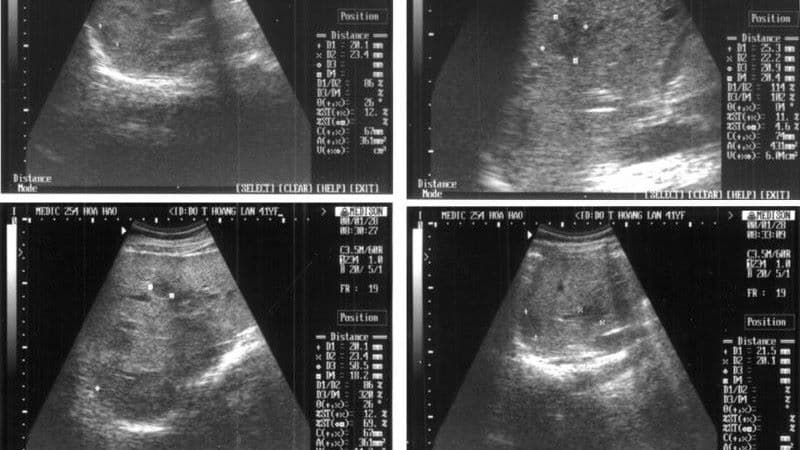

Thông qua hạch lao trên siêu âm, bác sĩ có thể đánh giá rõ hình thái và cấu trúc hạch. Cụ thể, hình ảnh hạch lao trên siêu âm thường cho thấy hạch tròn hoặc bầu dục, có thể mất cấu trúc xoang hạch bình thường. Một trong những đặc điểm hạch lao trên siêu âm điển hình là vùng giảm âm hoặc trống âm bên trong do hoại tử bã đậu. Ngoài ra, siêu âm còn phát hiện tình trạng hạch dính thành mảng, viêm quanh hạch và phù nề mô mềm xung quanh.

Khi đánh giá hạch lao trên siêu âm, bác sĩ thường dựa vào hình dạng, cấu trúc bên trong và mức độ viêm xung quanh hạch. Dưới đây là những đặc điểm điển hình, dễ nhận biết:

Hình dạng và kích thước

Khi quan sát hạch lao trên siêu âm, bác sĩ thường thấy hạch có kích thước to hơn bình thường, đường kính có thể từ 1cm đến vài cm. Hạch thường có dạng bầu dục hoặc tròn, tuy nhiên kích thước giữa các hạch trong cùng một vùng có thể không đồng đều.

Vỏ hạch dày và không đều

Quá trình viêm mạn tính khiến vỏ hạch dày lên và trở nên không đều. Trên siêu âm, đường viền hạch có thể không còn mịn và rõ như bình thường.

Viêm và phù nề quanh hạch

Không chỉ bản thân hạch bị tổn thương, mô mềm xung quanh cũng có thể bị viêm. Trên siêu âm, vùng quanh hạch có thể tăng âm và ranh giới không rõ do hiện tượng thâm nhiễm.